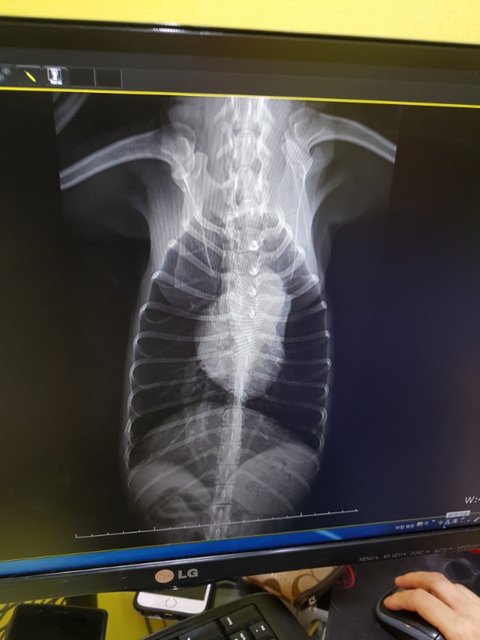

심장사상충..

그것도 너무나 많은 자충과 성충들이 온몸에 퍼져있다고 합니다.

보기드물게 폐에까지 성충이 자리잡고 있다고 합니다.